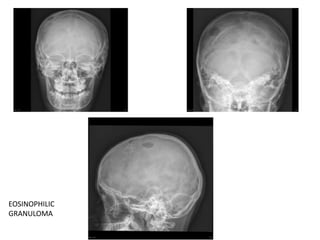

Histiocytosis X

( Eosinophilic granuloma, Letterer-Siwe disease, Hand-Schüller-Christian

disease)

• A single lytic lesion having sharp, non-sclerotic barder and bevelled edges is

characteristic of eosinophilic granuloma.

• A small bone in the center – Button sequestrum.

• Other two variants have larger, multiple and punched out lesions

EOSINOPHILIC

GRANULOMA

Malignant lesions • Primaryosteosarcoma – gross destruction of the bone with well defined margins and soft-tissue component • Metastasis • Intacranial mass lesions may present as lytic skull lesion Neurofibromatosis is a rare cause of lytic skull lesion – not due to neurofibroma, but due to mesenchymal defect. Histiocytosis X ( Eosinophilic granuloma, Letterer-Siwe disease, Hand-Schüller-Christian disease) • A single lytic lesion having sharp, non-sclerotic barder and bevelled edges is characteristic of eosinophilic granuloma. • A small bone in the center – Button sequestrum. • Other two variants have larger, multiple and punched out lesions